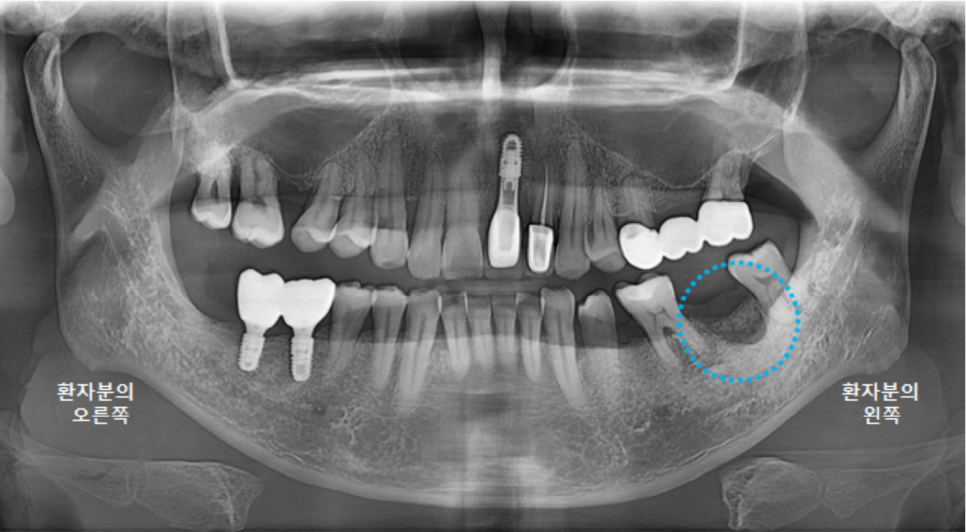

깨끗하게 뿌리조각과 염증을 제거하고 파노라마 엑스레이를 촬영했습니다.

(사진은 왼쪽어금니 발치와 오른쪽 어금니 수술 이후 촬영한 사진입니다^^)

뼈가 많이 녹아 있는 상태여서, 나중에 임플란트 식립시에 뼈이식이 꼭 필요할 것으로 보입니다.

치유가 잘 될 수 있도록, 치유를 촉진해주는 콜라겐 재료를 넣어주었습니다.